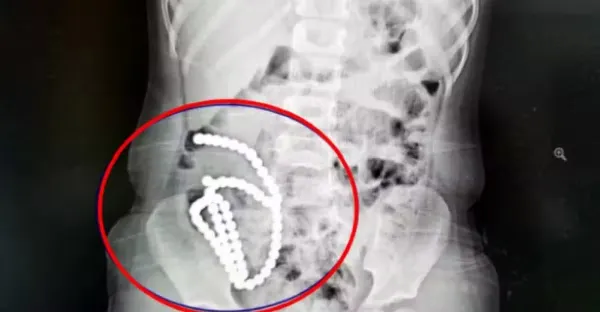

4歲妹照X光驚見「肚子整串白珠珠」 媽證實哥哥在玩!醫嘆:一輩子毀了